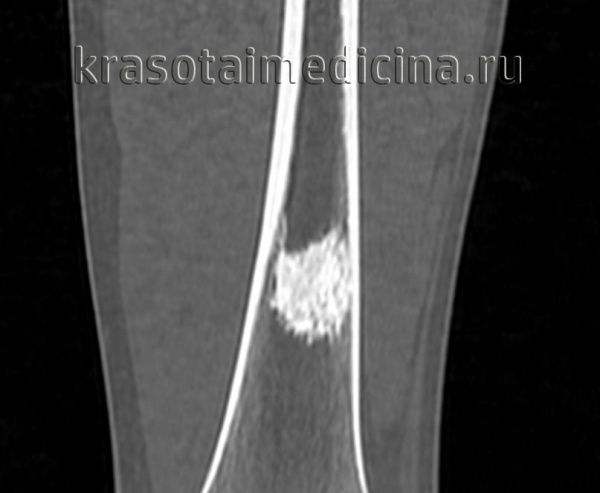

КТ левого бедра. Объемное образование (оссифицированная энхондрома) в нижней трети диафиза бедренной кости.

Хондрома

Доброкачественная опухоль кости, развивающаяся из хрящевой ткани. Может быть одиночной либо множественной. Локализуется хондрома в костях стопы и кисти, реже – в ребрах и трубчатых костях. Может располагаться в костномозговом канале (энхондрома) или по наружной поверхности костей (экхондрома). Озлокачествляется в 5-8% случаев. Обычно течет бессимптомно, возможны неинтенсивные боли. На рентгеновских снимках определяется округлый либо овальный очаг деструкции с четкими контурами. Отмечается неравномерное расширение кости, у детей возможна деформация и отставание роста сегмента конечности. Лечение хирургическое: резекция (при необходимости с эндопротезированием или костной пластикой), при поражении костей стопы и кисти иногда требуется ампутация пальцев. Прогноз благоприятный.